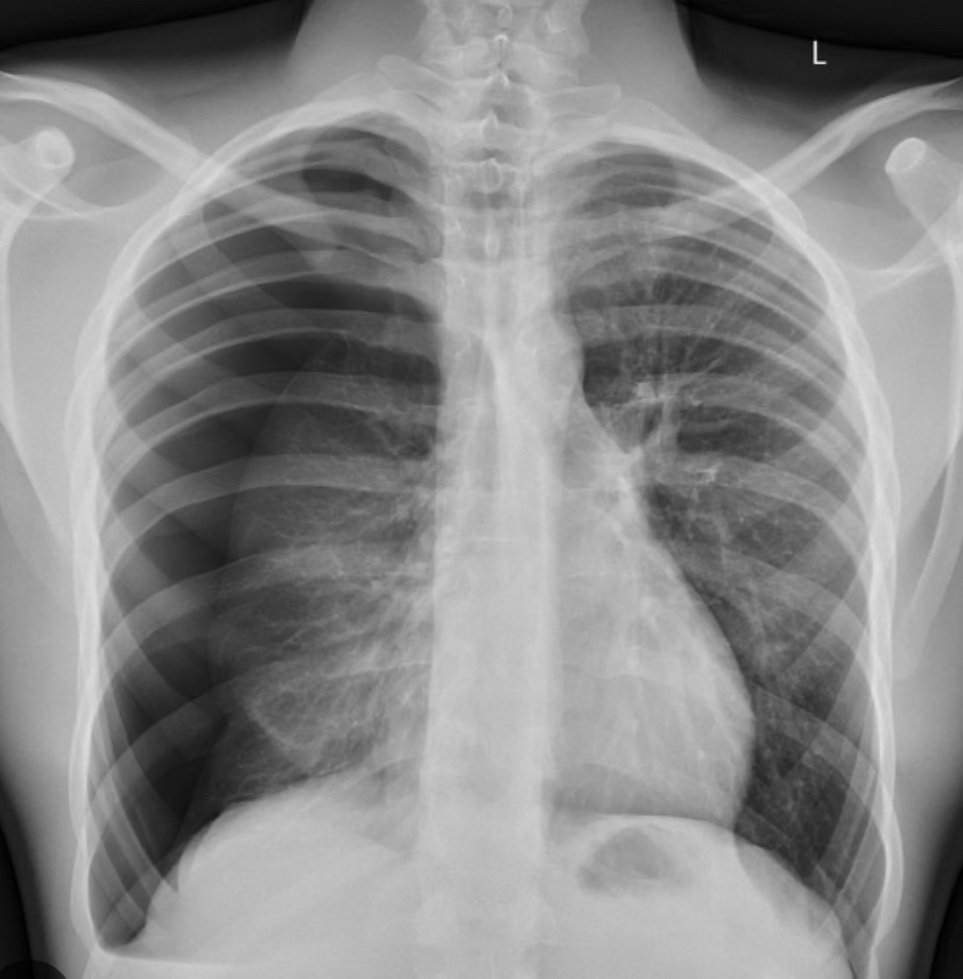

6. Catamenial Pneumothorax: this refers to the recurrent accumulation of air in the pleural cavity in women of reproductive age in the absence of concomitant respiratory disease. Typically pneumothorax occurs 72 hours before or after the periods. It caused by the implantation of ectopic endometrial tissue in the pleural space,as a part of endometriosis. It caused pneumothorax more often on the right side. To make this diagnosis it is necessary to have two episodes of pneumothorax associated with menses.

Treatment- take me to include Pleurodesis, surgery to resect out the endometrial tissue adherent to the pleura followed by oral contraceptive pill treatment.